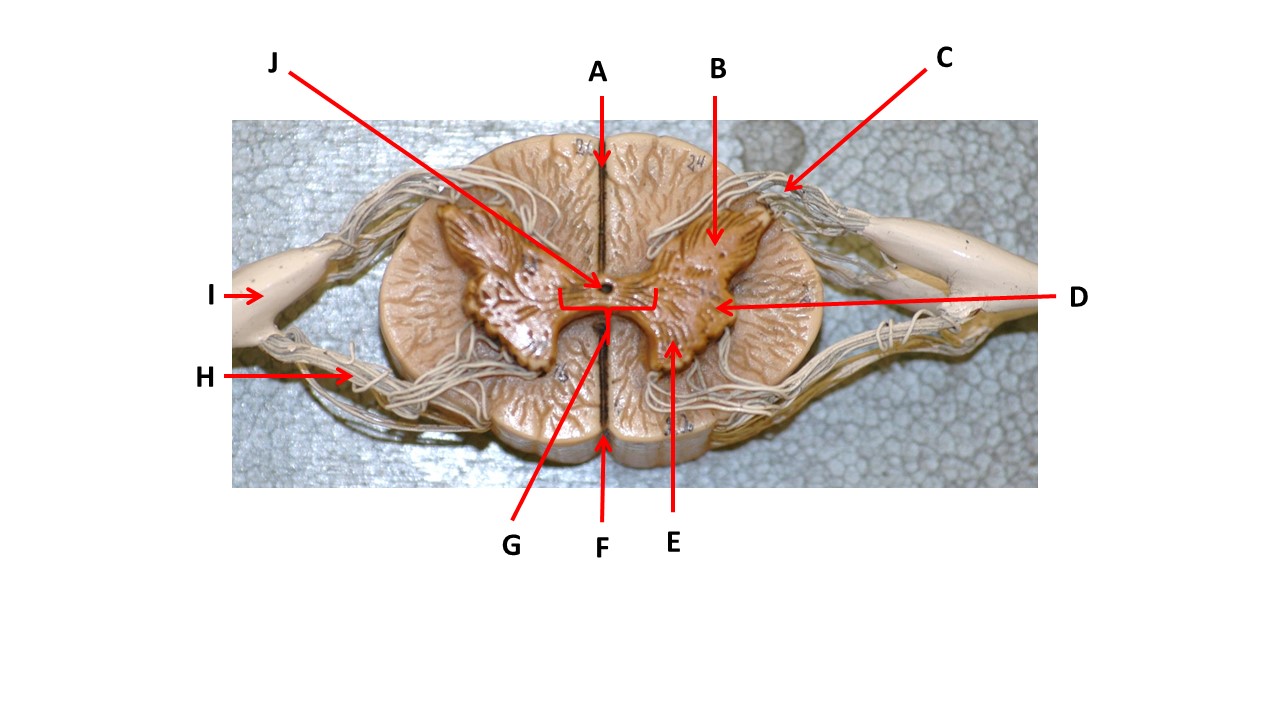

Name the region of tissue surrounding the tip of arrow E.

Name the region of tissue surrounding the tip of arrow B.

Name the region of tissue surrounding the tip of arrow J.

Name the region of tissue surrounding the tip of arrow E.

lateral horn

Name the region of tissue surrounding the tip of arrow N.

dorsal column

Which structure(s ) would be found in the area at the tip of arrow D.

cell bodies of interneurons

Name the region of tissue surrounding the tip of arrow E.

ventral horn

Name the region within bracket G.

gray commisure